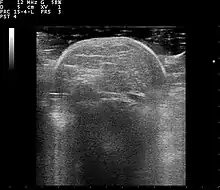

Familial multiple lipomatosis is usually diagnosed through a physical exam via palpation, medical history and imaging studies such as ultrasound, CT scan, or magnetic resonance imaging (MRI). A CT scan is an imaging method that uses x-rays to create images of cross sections of the body, while an MRI uses powerful magnets and radio waves to create images of lipomas and surrounding tissues.[3] Both tests are useful to establish the diagnosis of multiple symmetric lipomatosis, although magnetic resonance imaging provides more details and may be used when lipomas are large, deep, or have infiltrated muscle fibers or nerves. In some cases, a biopsy of the lipomas may be necessary to confirm the diagnosis.[3]